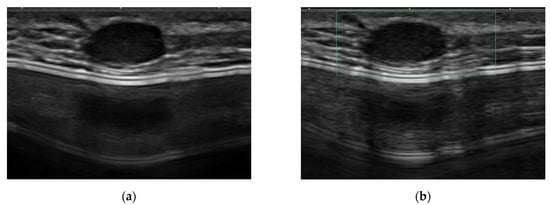

The other six symptomatic lesions manifested as palpable lumps in the reconstructed breast. Postoperative MRI detected all symptomatic mass lesions as suspicious lesions. Using ultrasound, four lesions (66.7%) were detected as suspicious lesions, while the other two were classified as BI-RADS category 2 and 3 lesions, respectively. The lesion classified as BI-RADS category 2 was initially considered as an epidermal inclusion cyst by ultrasound (Figure 4), and the lesion category 3 was considered as fat necrosis. However, both lesions showed a suspicious enhancement in MRI and were upgraded to BI-RADS category 4. The lesion detectability rates of ultrasound and postoperative MRI for symptomatic recurrent mass lesions showed no significant difference (p = 0.140.)

Figure 4.

Symptomatic recurrent case mimicking a benign epidermal inclusion cyst. A 27-year-old female patient who underwent right-breast skin-sparing mastectomy with reconstruction with a silicone implant bag for mucinous carcinoma (grade 2, luminal type) 48 months ago. (a,b) Using ultrasound as a method of routine surveillance, an oval circumscribed hypoechoic mass with posterior enhancement was noted in the reconstructed breast, where the patient complained that a palpable lump was present. Since the mass is accompanied by skin tract and showed no vascularity on the Doppler scan, it was considered to be an epidermal inclusion cyst. (c,d) At postoperative MRI, the mass showed fast enhancement on the early dynamic phase fat-saturated T1-weighted image with a washout kinetic pattern. Based on the finding of the MRI scan, the category of the mass was upgraded to category 4, and it was confirmed as invasive ductal carcinoma by surgical excision.